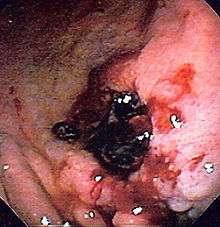

| Endoscopic image of a posterior wall duodenal ulcer with a clean base, which is a common cause of upper GI hemorrhage. | |